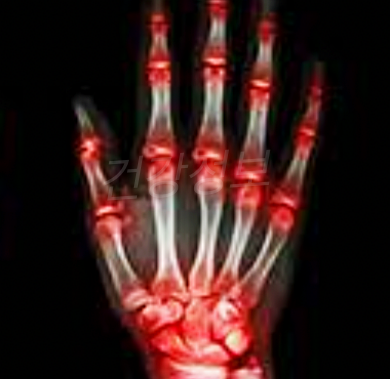

류마티스 관절염 초기증상

손의 경직, 부종, 통증, 발열, 권태감

류마티스 관절염은 신체 면역 체계 이상이 생겨 신체 조직을 공격했을 때 발생하는 면역 질환에 대해 발생하는 만성 질환입니다. 염증성 질환 증상으로 주로 손, 허리, 발에서 발생합니다, 무릎 관절의 통증, 경직, 부종을 일으킵니다.

우리 몸의 관절을 파괴 할뿐만 아니라 피부, 눈, 폐, 심장, 혈관 등 신체 기능을 손상시킬 수도 있습니다.

류마티스 관절염은 자가 면역 질환의 일종으로 면역 세포의 기능 부전에 의해 관절에 필요 이상의 염증 반응을 일으 킵니다. 류마티스 관절염은 염증이 계속되면 관절 영역을 넘어 온몸에 퍼질 가능성이 있기 때문에 특별한주의가 필요합니다.